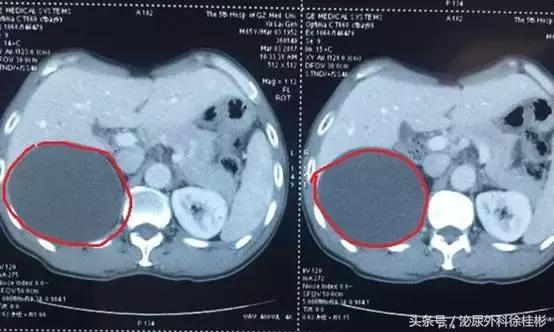

红色圈圈所指就是囊肿的位置

一听到“肿”字徐大叔心里就慌了,囊肿囊肿,会不会跟肿瘤有关系啊。于是一刻也没耽搁,赶紧到肾内科咨询。医生看了片子之后告诉徐大叔,囊肿和癌不一样,但目前囊肿比较大,直径有5-6cm,需要尽快治疗。

之后,肾内科医生将徐大爷转介到了我们泌尿科。经过一番考虑之后,决定给徐大叔行腹腔镜切除手术,只用了不到半小时的时间,手术就顺利完成。术后徐大叔恢复情况良好,标本术后完整复原,可装水200多毫升。